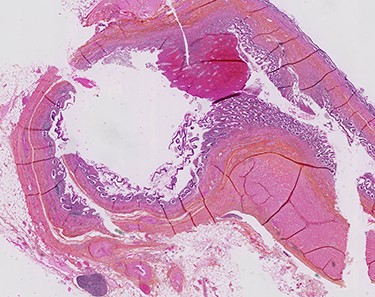

A diagnostic laparoscopy was performed and revealed a whitish granulomatous appendix and a thickened caecum with chronic-like peritoneal adherences. Because of the neoplastic suspicion and anatomic features, a right hemicolectomy with intracorporeal anastomosis was performed after reaching a surgical consensus. The pathology report confirmed a secondary appendicitis on multiple inflamed appendiceal diverticula (see Fig. 2). No neoplasm was identified. The patient was discharged without complication.